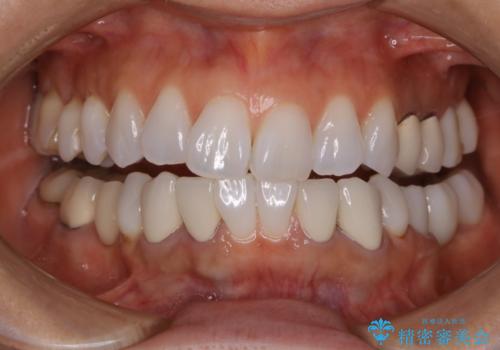

オフィスホワイトニングで、歯を白く!

- ホワイトニングで、ご自身の歯を白くしたいと来院されました。

医院で行う、オフィスホワイトニングで歯が白くなり、喜んでいただけました。